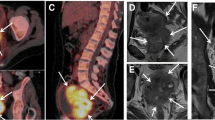

In the spectra obtained from our uterine cervical tumours, it was possible to identify the signals of Glx, m-Ins, tCho, tCr, NAA, Ala, Lac, and Lip, as shown in Fig. 1a. Quantification was obtained for those metabolites who satisfy the condition of Cramer-Rao lower bounds less than 20% and therefore for tCho, Glx, NAA, and Lip. Short TE (28 ms) spectra presented a different metabolic pattern in the two populations GR and NR/PR. In particular, as a first result, we observed that the mean Lip value in GR patients (100 ± 50 mM) was significantly lower than in PR-or-NR patients (270 ± 50 mM) (p = 0.040). Representative spectra are shown in Fig. 1a (low lipid level, L) and Fig. 1d (high lipid level, H). Long TE (144 ms) spectra analysis showed absence or low level of Lac at 1.3 ppm, thus excluding lipid overestimation in the quantitative analysis.

Representative spectra (echo time 30 ms) of the two groups: (a) low and (d) high lipid level, corresponding to good responder patients (GR) and partial or nonresponder patients (PR-or-NR), respectively. Peak assignments: Glx, Glutamine plus glutamate; m-Ins, Myo-inositol; tCho, GPC plus PCho or total choline; tCr, Creatine plus phosphocreatine; Ala, Alanine; Lip, Lipids; Lac, Lactate. T2-weighted paraaxial (b, e) and sagittal (c, f) images of the two cases

Moreover, a significant difference was also observed in tCho distribution. In the GR group, the mean tCho peak value (4.2 ± 1.9 mM) was significantly higher than in the PR-or-NR group (1.8 ± 0.4 mM) (p = 0.040). Finally, we also observed a significant difference in the Lip/tCho ratio with higher values in PR-or-NR patients (30 ± 20) than in GR patients (160 ± 60) (p = 0.040). Figure 2 shows the box plots of the signals of Lip (a), tCho (b) and of the ratio Lip/tCho (c), and Table 3 summarises the data obtained.